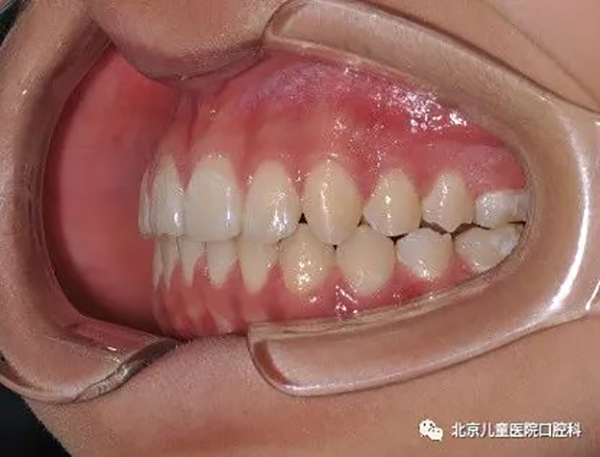

3、牙列整体远移,见于轻度牙列不齐,轻度牙齿前突,或轻度地包天的病例。

治疗前

治疗中